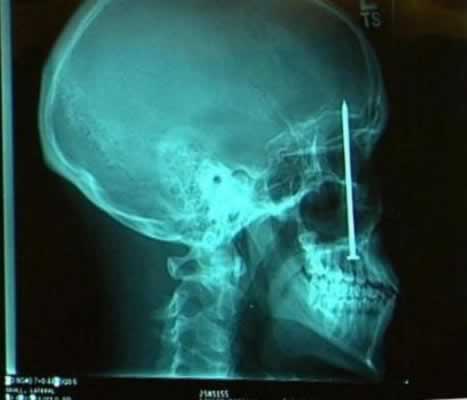

9. Paku

Sebuah insiden dialami oleh Patrick Lawler ketika bekerja di sebuah tempat peristirahatan di Pegunungan Colorado. Sebuah pistol paku menembakkan pelurunya pada kayu yang berada di dekat Lawler. Akibatnya, paku sepanjang 4 inchi mengarah masuk ke mulut Lawler.

10. Kunci